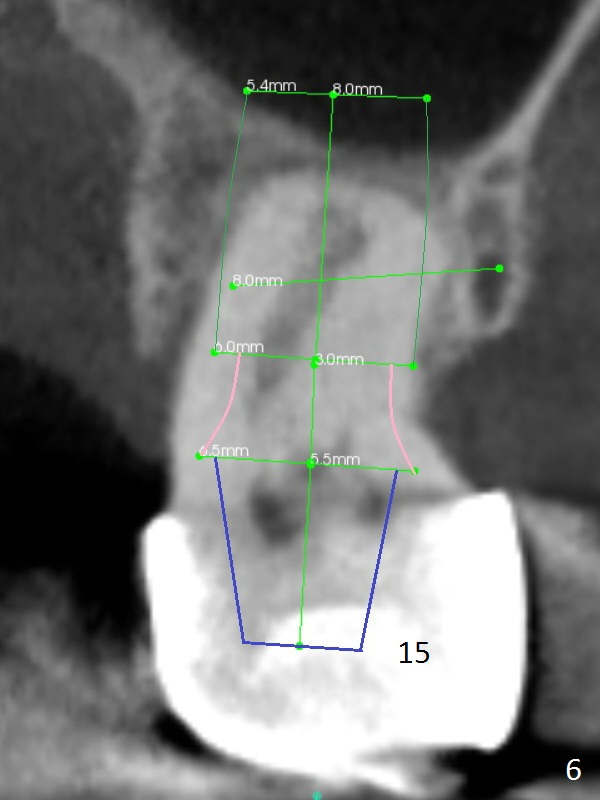

While the 64-year-old woman is undecided on the lower right quadrant treatment, she has had periodic pain and swelling in the upper left quadrant (Fig.1). CBCT sagittal sections show periapical radiolucency at #13 and bone loss distal to #15 palatal root (Fig.2,7). Endodontic treatment is the 1st option to save the long bridge (#9-15, Fig.1).

More thorough option is to section between #11 and 12, remove #13 and 15 retainers and determine salvageability of #13 and 15 abutments. Place implants between #12 and 15 if necessary (Fig.3-6 coronal sections; B: buccal).